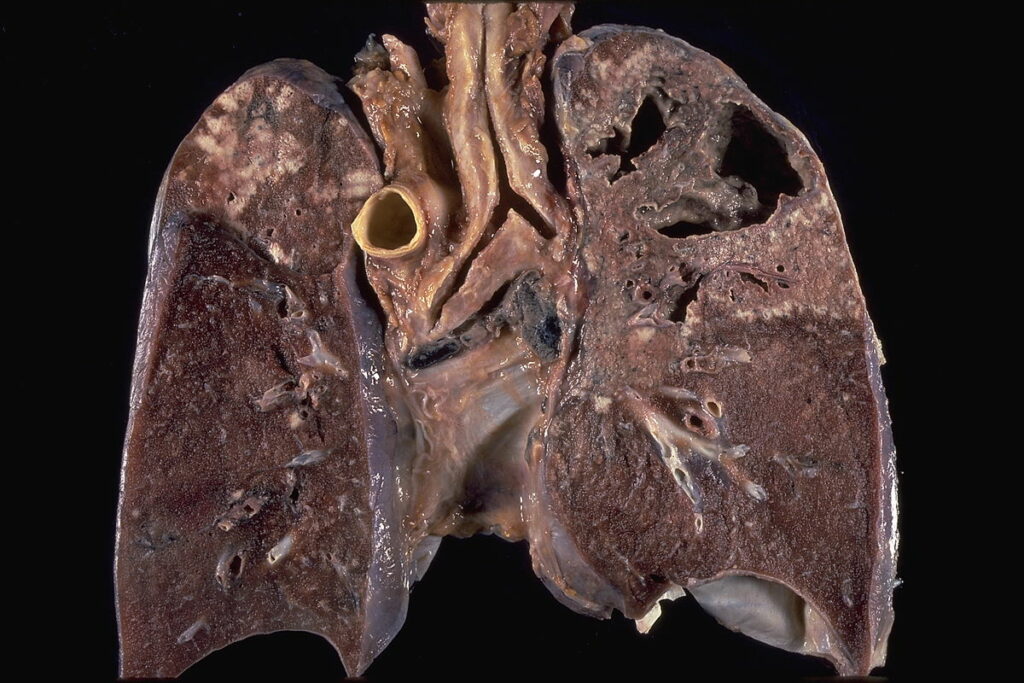

„Tuberkulózu se nedaří a zřejmě i nikdy nepodaří vymýtit vzhledem k tomu, že je infikována asi čtvrtina světové populace, především v méně rozvinutých zemích, kde navíc narůstá odolnost proti antituberkulotikům.